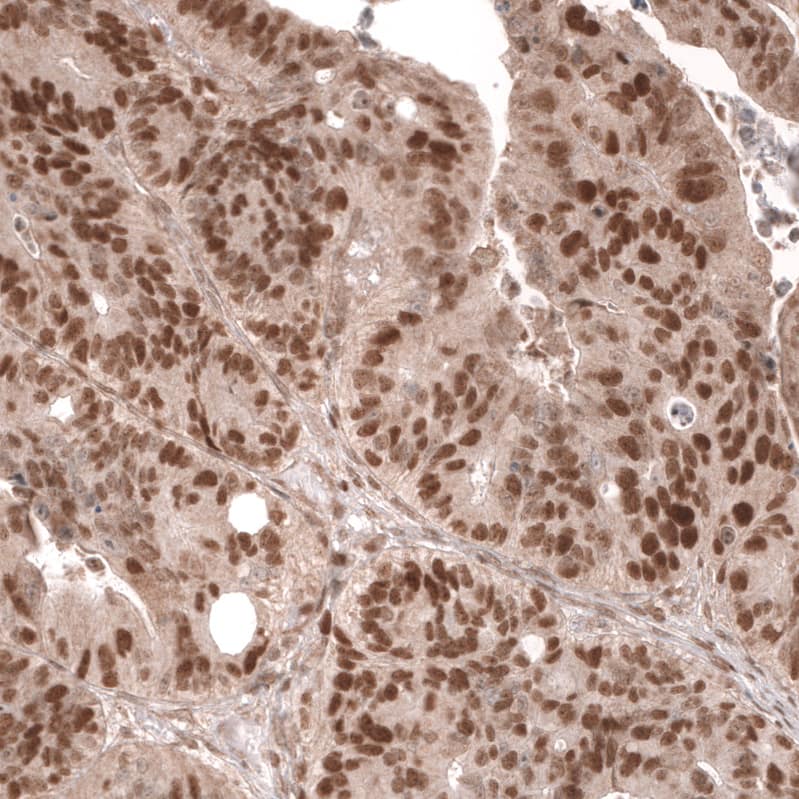

Immunohistochemistry-Paraffin: MSH6 Antibody (CL13844) [NBP3-24582]

Staining of human ovarian cancer (high grade serous carcinoma) shows strong nuclear positivity in tumor cells.